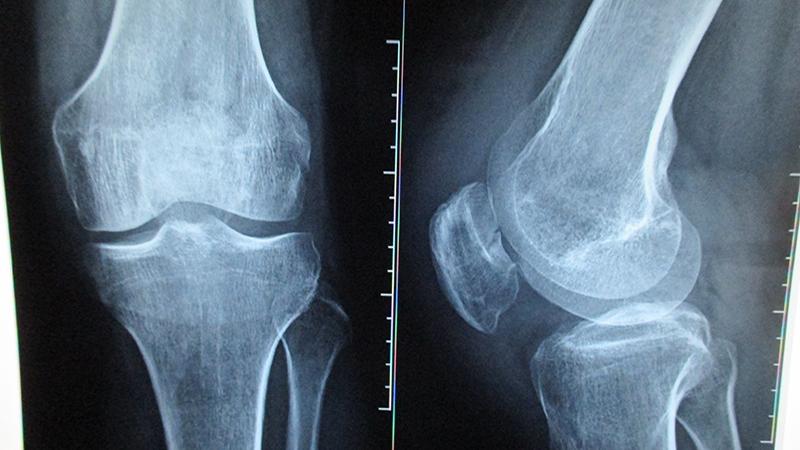

- Вторая стадия. Боль усиливается, появляются признаки воспалительного процесса. На этом этапе рентгенография позволяет увидеть пораженный участок и его отделение от здоровых тканей. Часто в этот период пациентам ставят неверный диагноз – синовит.

- На последней стадии происходит полное отслаивание некротизированной области. У человека наблюдаются интенсивные боли, усиливаются симптомы воспаления. Рентгеновские снимки четко демонстрируют дефект в области коленного сустава и поврежденный хрящевой фрагмент.

- рентгенография;